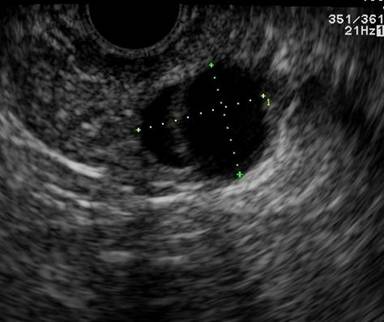

A 42-year-old female was referred for evaluation of an incidental pancreatic tail cyst found on CT (Figure 4). Initial EUS assessment revealed a 17x10 mm anechoic and thinly septated cyst. The FNA aspirate was a thin clear fluid with a CEA level of 9.4 ng/mL. Cytology revealed a few clusters of bland epithelial cells (mucicarmine negative) and debris. Given the possibility that this could still represent a mucinous cystic neoplasm, surveillance EUS was recommended. One year later, EUS revealed a 15x12 mm thinly septated cyst (Figure 5); however, the fluid was slightly viscous, with an elevated CEA level of 9,646 ng/mL. Cytology revealed numerous hemosiderin-laden histiocytes and rare ductal epithelial cells. Given suspicion for mucinous cystic neoplasm, the patient underwent laparoscopic resection, and surgical pathology verified a mucinous cystic neoplasm with low grade dysplasia.

Figure 5. Corresponding EUS image revealing a finely septated 15 mm pancreatic cyst. (Patient #2). |